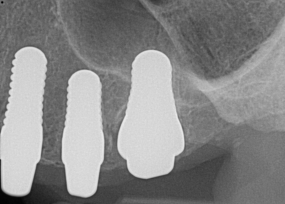

Fig 17. 12-week postoperative radiograph.

Figure 17

Essentially, after integration and evaluation of soft tissue at 12 to 16 weeks subsequent to surgical placement of the ceramic implant, the implant is treated similarly to a natural tooth receiving a long-term restoration, and the protocol is the doctor's choice for soft-tissue management at the time of the final impression. Radiographic examination in Figure 8 and Figure 9 revealed that bone volume and soft tissue were preserved, primarily due to exceptional biocompatibility and the PRF biologics implemented after the atraumatic extractions.

The final impression appointment follows the light-load phase, provided the implant is stable and the soft tissue is acceptable to the clinician. Polyvinyl putty and light-body impression materials were used in this case; analog casts and final full-zirconia full crowns were fabricated (Figure 16). The patient provided feedback that chewing was comfortable and without food impactions. Keratinized gingival cuff was developed, and natural-tooth contours for the restorations mimicked what is normally found in human dentition. The healed bone surrounding the ceramic dental implant was similar in density and crestal levels in comparison with the adjacent natural teeth, evident in the radiographic evaluation (Figure 17). Final long-term restorations at the gingival crest and restoration interfaces were also consistent in optimum periodontal health and gingival height. Arch-form integrity was upheld and occlusion was managed; osseointegration and light-load principles optimized the success of the restorations, and an acceptable, harmonious esthetic outcome was achieved for the patient.